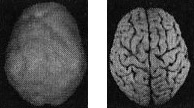

Когда мозг работает правильно, у вас все хорошо Когда мозг не в порядке, в жизни начинаются неприятности Именно мозг определяет эффективность вашей жизни. Этот принцип выглядит простым, но на самом деле он достаточно неоднозначный и может вызвать тревожность. Основная идея заключается в том, что мозг должен функционировать оптимально. Когда он работает правильно, вам легче оставаться эффективным родителем, ребенком, партнером, другом, коллегой, менеджером или общественным деятелем. Когда мозг функционирует правильно, вы имеете полный доступ к своему истинному Я. С другой стороны, если мозг болен, начинаются трудности в работе, отношениях, наедине с собой и в компаниях. Становится труднее проявлять свои лучшие качества и сильные стороны, нередко люди действуют вопреки своим ценностям, целям и представлениям о нравственности. Принцип 2 Когда мозг работает правильно, у вас все хорошо. Когда мозг не в порядке, в жизни начинаются неприятности Я вывел этот принцип в результате интерпретации сотен томограмм моих пациентов, поскольку не только читаю сканы, но и напрямую работаю с людьми и их семьями, изучаю историю их жизней. Уже в самом начале моей работы с томографией стало очевидно, что существует зависимость между качеством функций мозга на сканограммах и умением моих пациентов принимать решения, ставить цели и поддерживать отношения. Анализируя снимки, я стал размышлять о разнице между двумя типами поведения, которые я называю волевым поведением (управляемым силой воли) и мозговым поведением (управляемым неконтролируемыми импульсами мозга). Реализовывать команды силы воли возможно только при здоровом мозге, поскольку лишь он позволяет людям делать осознанный выбор и в любой ситуации действовать себе во благо. Волевое поведение продуктивно, оно способствует достижению целей, которые вы сами поставили. Например, приняв решение поступить в медицинский институт, человек должен очень усердно учиться, чтобы выдержать сложные экзамены. Прежде чем объяснить, что такое «мозговое поведение», я хочу сделать небольшое отступление, чтобы рассказать о томографии, которую мы проводим в наших клиниках. Она называется ОЭКТ — однофотонная эмиссионная компьютерная томография — и относится к области ядерной медицины, то есть для оценки кровообращения и схем активности мозга используются крошечные дозы радиоизотопов. Сканограммы ОЭКТ отличаются от типичных анатомических снимков МРТ и КАТ, которые показывают строение мозга. ОЭКТ показывает только степень активности разных областей мозга — то, как он работает. Результаты сканов ОЭКТ очень легко интерпретировать. Нужно посмотреть на области мозга, которые работают хорошо, области, которые функционируют чересчур активно («перегреты») и на недостаточно активные области. Затем мы сравниваем изучаемый скан с большой базой данных здоровых и абнормальных томограмм. В этой книге используют трехмерные снимки мозга двух видов. Первый — это трехмерные снимки поверхности, которые фиксируют верхние 45 % активности мозга. На них показано кровообращение в коре мозга и подкорковых областях. По этим снимкам мы определяем области нормального кровообращения и области со сниженным доступом крови. С помощью таких томограмм выявляют инсульты, травмы и ущерб от наркотиков. Снимок здорового мозга должен показать ровную симметричную активность по всей поверхности коры мозга (рис. 2.1 и 2.2). Трехмерное изображение поверхности здорового мозга ОЭКТ (вид поверхности сверху и снизу) Рис. 2.1 Вид сверху Полная симметричная активность ![]() Рис. 2.2 Вид снизу Полная симметричная активность ![]() Сниженная активность выглядит на подобных сканах как дыра или вмятина. Эти «дыры» и «провалы» не означают, что активность мозга в этих местах совсем на нуле, она просто снижена, так как компьютер настроен показывать только верхние 45 % активности. Все, что меньше этого значения, выглядит как дыра или вмятина. Порог в 45 % выбран, поскольку он соответствует двум стандартным отклонениям от нормы [1] и, согласно нашим данным и данным других исследователей, является оптимальным для диагностических целей. Второй тип томограмм — это трехмерные функциональные снимки, в которых компьютер сначала вычисляет среднюю активность мозга, а затем показывает верхние 15 % активности. Они помогают увидеть гиперактивные области, что полезно в диагностике припадков, разных типов тревожности и депрессии. Здоровый трехмерный функциональный снимок (рис. 2.3 и 2.4) должен показывать активность (белым цветом) в задней части мозга (мозжечке) и визуальной, или затылочной, коре и среднюю активность в остальных местах (показано сеткой). Трехмерное изображение функциональной активности здорового мозга ОЭКТ (вид поверхности сверху и снизу) Рис. 2.3 Вид сверху ![]() Рис. 2.4 Вид сверху ![]() Примечание: В тексте книги будут использоваться иконки, которые помогут читателю понимать сканограммы и увидеть их отличия от нормы. Рис. А состоит из двух иконок: трехмерного изображения поверхности здорового мозга, вид сверху; и модели мозга с той же самой перспективы. ![]() Рис. Б показывает трехмерный снимок поверхности здорового мозга, вид снизу, а нижняя иконка — это модель мозга с той же перспективы. ![]() Рис. В показывает трехмерную картину активности здорового мозга, вид сверху, а ниже показан мозг в этой проекции. ![]() |